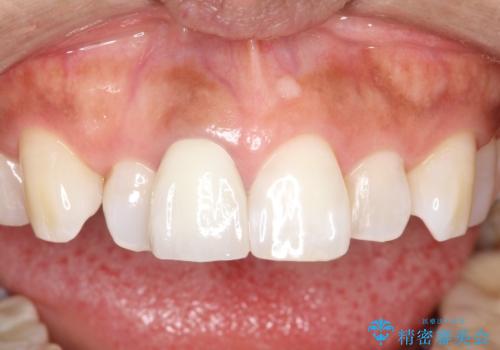

仮歯の期間にホワイトニングも行っていただいてから、色合わせをして最終的なかぶせものを入れています。